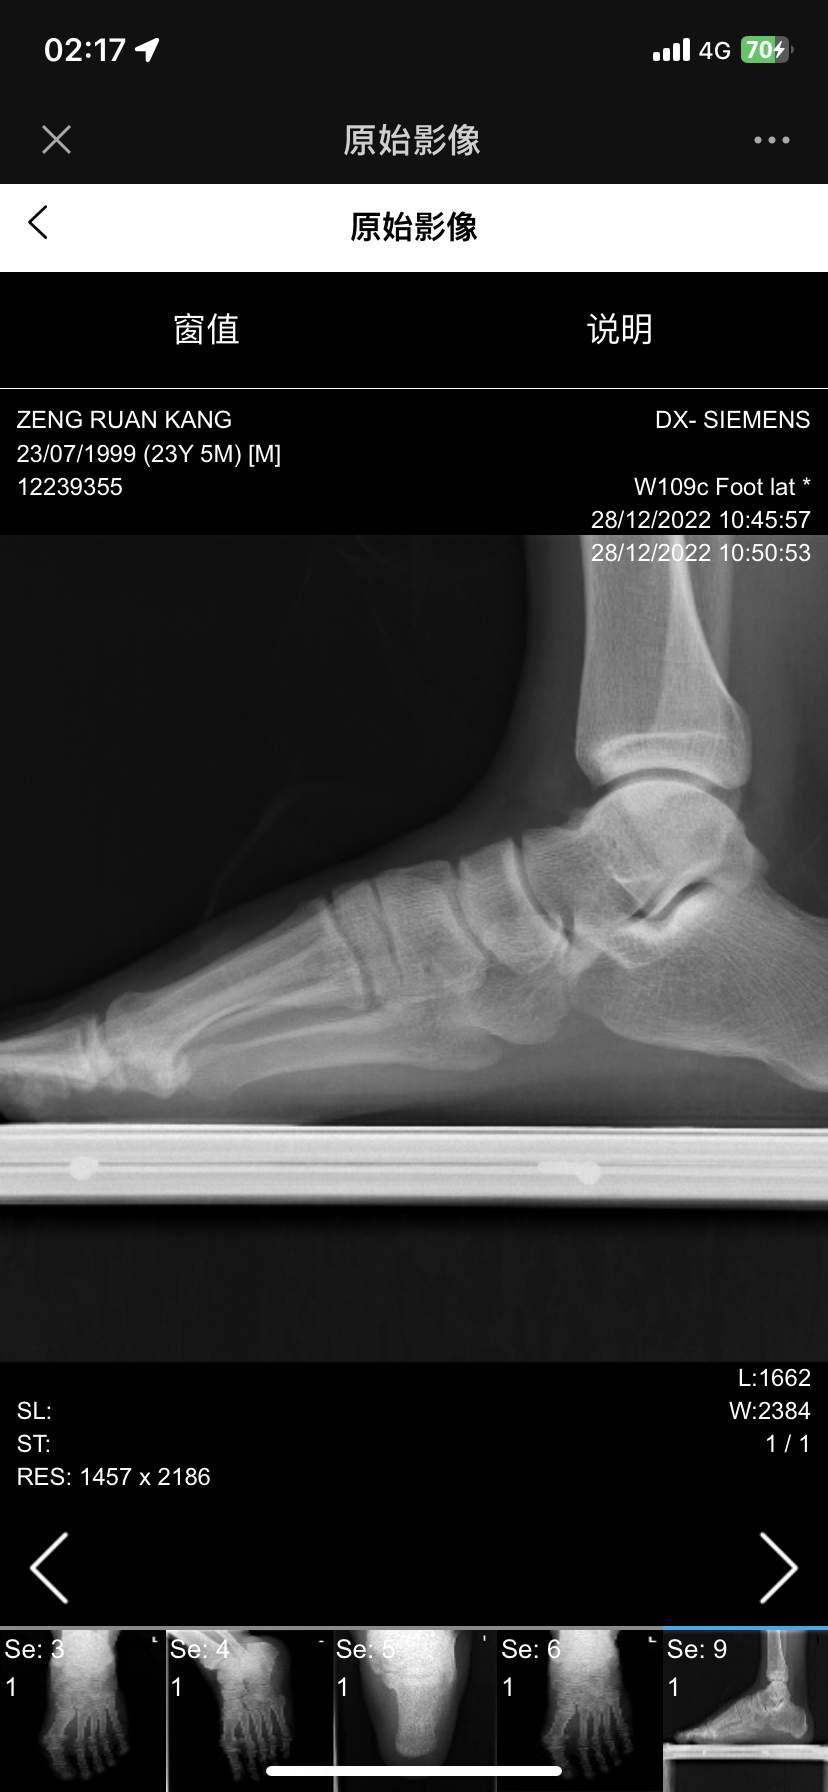

扭伤后组底外侧跟骰关节处疼痛五年,骰骨综合征?

患者五年前跖屈内翻扭伤,痊愈后才注意到足底外侧骰骨处疼痛,行走时尤甚,随着活动增加而加重,这几年找了很多足踝大夫都看不出来,因为b超磁共振和x光没有显示任何结构问题,也没有炎症水肿的表现,活动度也基本正常,内外翻跖屈背曲无痛,尝试过药物,封闭,针刀,冲击波等效果均不佳,因疼痛影响生活轻度抑郁,老师们考虑这是什么病?